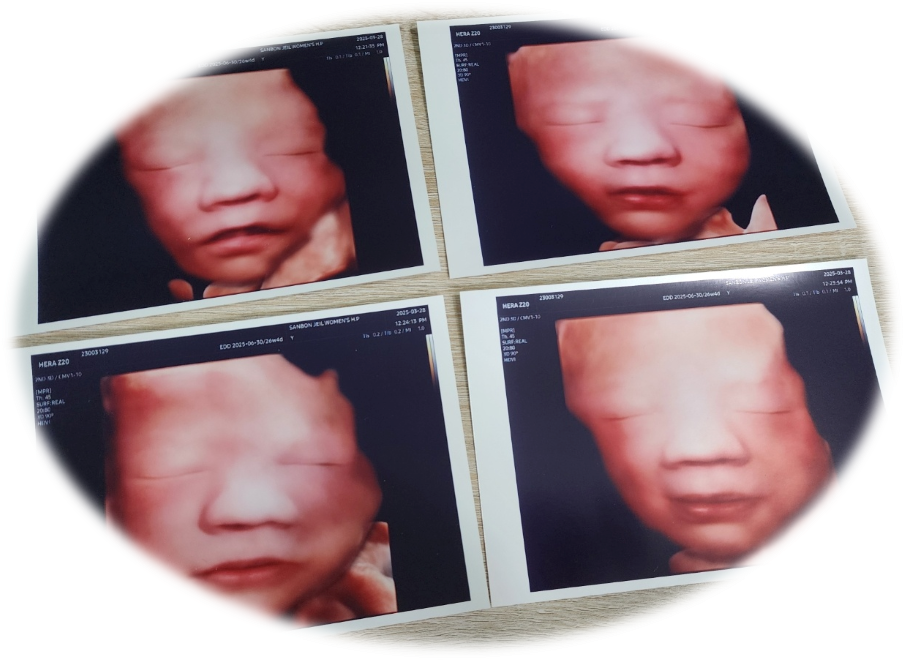

3D 입체초음파 사진

몇 번의 시도 끝에 어렵게 촬영한 사진이 바로 이것입니다.

카톡으로 받아보니 생각보다 얼굴 윤곽이 또렷하게 잘 나와서 좀 놀라기는 했습니다.

download.png [태아 '팡팡이' 3D 입체초음파 사진]

제가 추가로 받은 초음파 동영상을 편집하면서 보니, 초음파에서 보이는 얼굴을 그대도 보여주는 것이 아니라 보정(?)되는 게 아닐까 하는 생각이 듭니다.

우선 양쪽 눈과 입을 포인트로 찍으면 화면에 있던 쭈굴쭈굴(?)한 얼굴이, 아주 깔끔하고 선명하게 표현이 되는 것으로 보아 뭔가가 터칭 작업을 하는 것 같아서입니다.

여하튼 태아 초음파 사진을 보니 코는 딸애를 입은 사위를, 묘하게 반반씩 닮은 듯하네요.

태아 3D 초음파 사진은 나중에 태어난 후 얼굴과 비슷하다고 하니, 출산 후 어떨지 비교를 한번 해볼까 합니다.